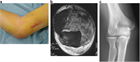

1. 肘関節脱臼・骨折などに伴う急性靱帯損傷で肘関節不安定性がある場合には、一次的靭帯修復を行うことが推奨される。

1. 投球動作などに起因する慢性靭帯損傷では、まず、理学療法などを中心にした保存的治療を行うことが推奨される。

1. 肘関節不安定性が持続する慢性靭帯損傷では、靭帯再建術を行うことが推奨される。